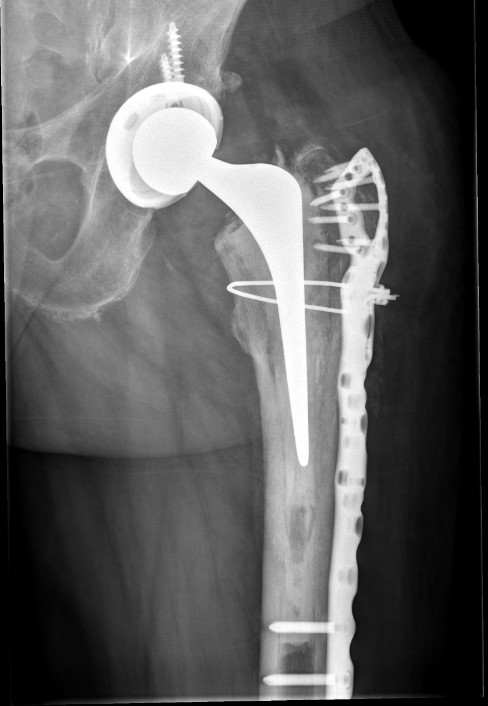

Revision uncemented arthroplasty with Zimmer cable plate

Long stem uncemented revision with plate + cortical struts